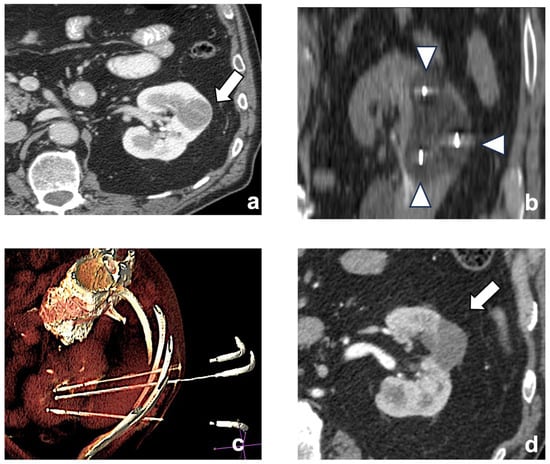

2.2. Procedures

2.3. Ablative Devices and Techniques

2.4. Imaging Guide